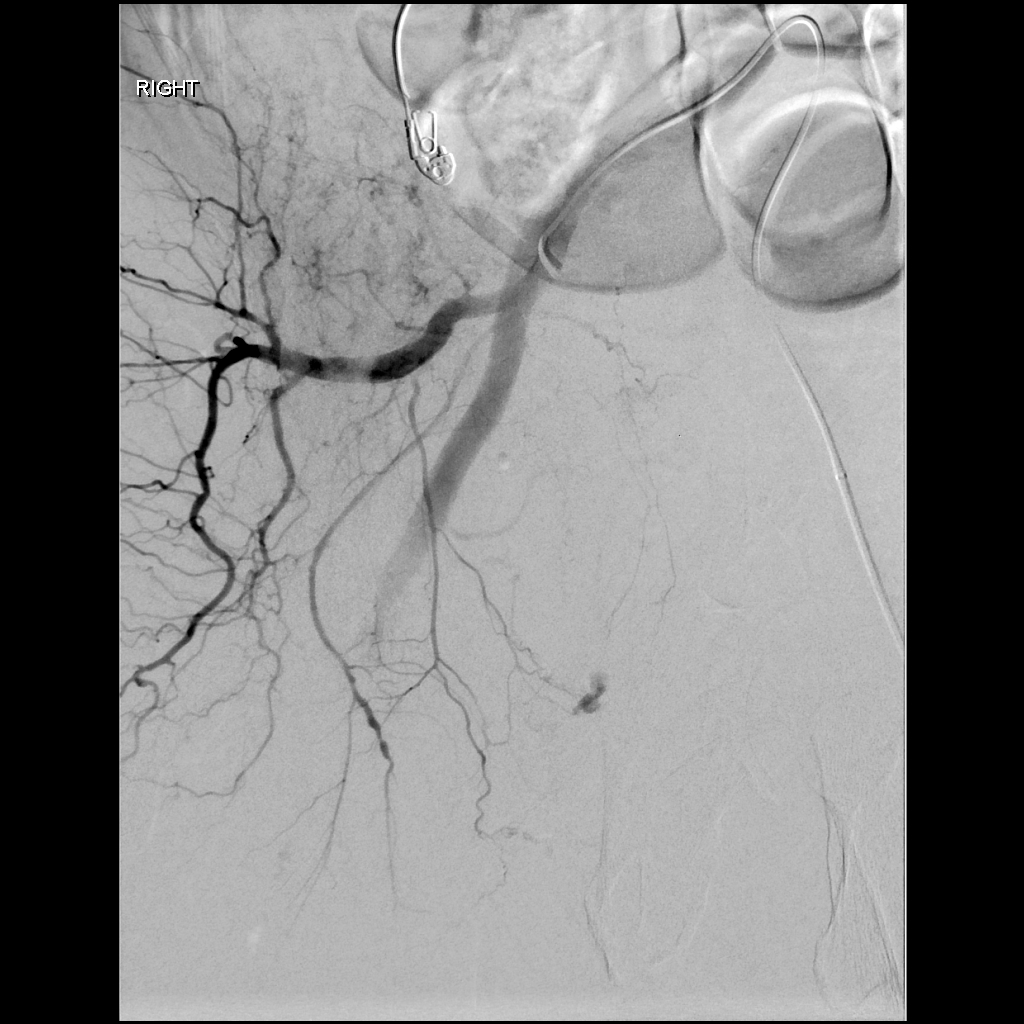

First day with LAVA-18 and it was quite the day. Our first case was a hypotensive patient with a pelvic fracture and active bleeding (with the LAVA coming off the delivery truck right to the angio suite and right into the patient). @SirtexMedical @thegestgroup